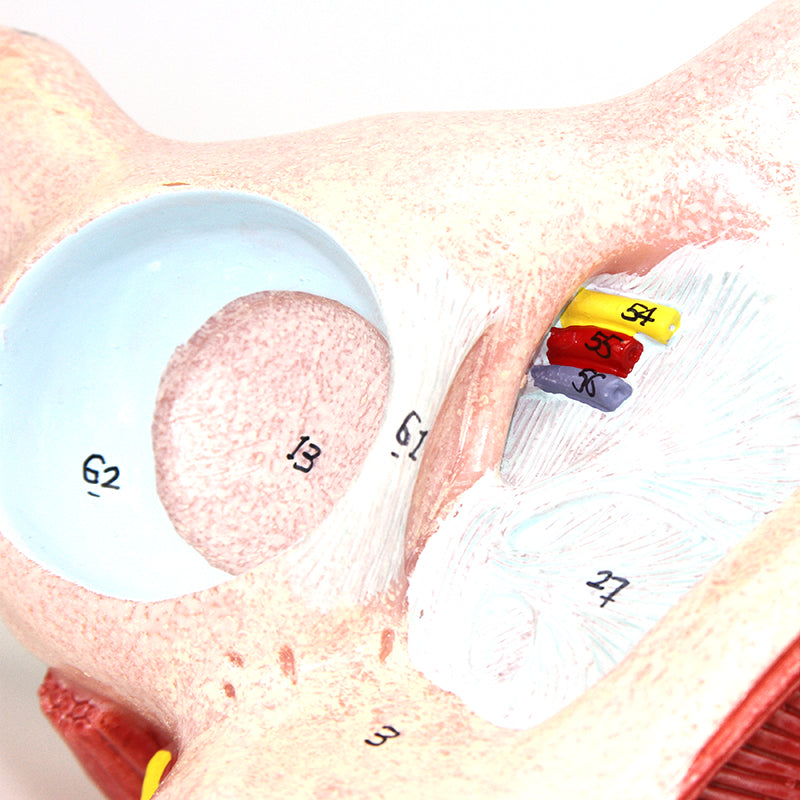

女性骨盤モデル(靭帯、血管、神経、骨盤底筋付き)

この実物大の女性骨盤は、仙腸靭帯、骨盤底筋、神経網および仙骨血管とともに、骨盤の外性器および内性器の構造を手描きで示しています。筋肉や靭帯の筋理を細かく描写しており、このモデルに高品質で詳細な印象を与えています。このモデルは女性の骨格系を理解するための優れた学習教材であり、すべての学生に適しています。さらに、神経痛、筋肉の緊張、靭帯の損傷を患者に説明する際にも役立ちます。拡張現実を用いたインタラクティブな三次元解剖モデルと併用することで、学習を促進し支援する優れたツールとなります。このプラットフォームは、学生が個々の器官の構造を比較・対照しながら解剖モデルの比較分析に取り組むことを可能にします。また、この取り組みは継続教育の場を提供し、すべての学生が解剖学、生理学および病理生理学の知識を深める機会を提供します。

女性骨盤モデル(靭帯、血管、神経、骨盤底筋付き)

この実物大の女性骨盤は、仙腸靭帯、骨盤底筋、神経網および仙骨血管とともに、骨盤の外性器および内性器の構造を手描きで示しています。筋肉や靭帯の筋理を細かく描写しており、このモデルに高品質で詳細な印象を与えています。このモデルは女性の骨格系を理解するための優れた学習教材であり、すべての学生に適しています。さらに、神経痛、筋肉の緊張、靭帯の損傷を患者に説明する際にも役立ちます。拡張現実を用いたインタラクティブな三次元解剖モデルと併用することで、学習を促進し支援する優れたツールとなります。このプラットフォームは、学生が個々の器官の構造を比較・対照しながら解剖モデルの比較分析に取り組むことを可能にします。また、この取り組みは継続教育の場を提供し、すべての学生が解剖学、生理学および病理生理学の知識を深める機会を提供します。